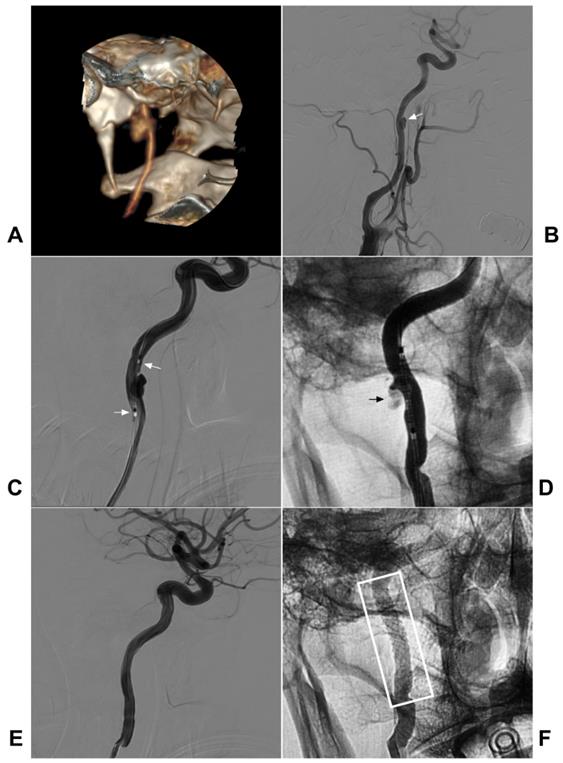

Dissection-related stenosis usually appears as a smooth and tapered narrowing that varies in severity and length depending on the extent of the dissection, and the occlusion demonstrates a tapered, flame-like appearance [15]. On DSA, antegrade and retrograde collateral obstruction channels, including the anterior and posterior communicating arteries and ophthalmic artery, can be seen in the acute phase of arterial occlusion, and rapid assessment of collateral circulation on DSA is thus necessary [46, 47]. A typical case is shown in Figure 2.

Figure 2

Traumatic extracranial ICA occlusion. A: CTA soft tissue reconstruction shows the left face injury in front of the ear. B: CT showed the left MCA high-density sign (arrow). C: CTA reconstruction showed maxillary bone fracture (black ellipse) and extracranial ICA occlusion (arrow). D: CTA reconstruction showed a thin intracranial MCA (asterisk). E: MRA showed the connections from AcomA and PcomA to MCA. F: Follow-up CT showed infarction of the left basal ganglia region. Abbreviations: AcomA: anterior communicating artery; CT: computed tomography; CTA: CT angiography; ICA: internal carotid artery; MCA: middle cerebral artery; MRA: magnetic resonance angiography; PcomA: posterior communicating artery